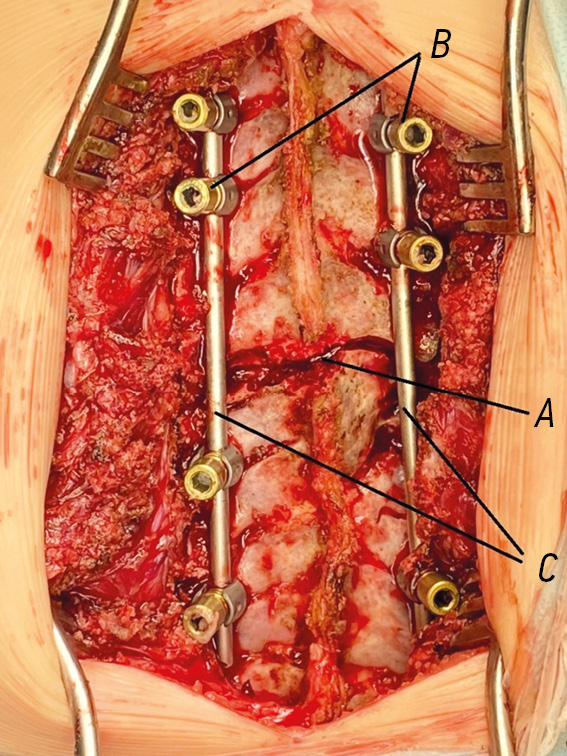

Fig. 4. Surgical intervention site after wedge osteotomy: A, vertebrectomy site; B, supporting elements installed on both sides of the deformity, with fixed bars; C, bars bent in accordance with the physiological profile of the spine after segmental correction

Surgical technique. A skin incision was made from the dorsal approach along the midline in the projection of the spinous processes of the vertebrae; thereafter, the dorsal structures of the vertebrae were skeletonized. Following visual control and radiography using X-ray contrast marks, the vertebrectomy site was determined, i.e., at the level of the apical vertebra. Channels were formed in the bodies of adjacent vertebrae for the installation of pedicle screws. If transpedicular fixation was not possible, laminar hooks were used. Vertebrectomy was started after X-ray control of the correctness of the position of supporting elements. The transverse process of the apical vertebra, a part of the arch on the convex side of the deformity, and a fragment of a rib were removed over a distance of 2.0 cm from the costovertebral joint. Then, wedge-shaped resection of the vertebral body was performed transpedicularly using small curets and conchotomes with the apex facing the concave side of the curvature, while the cranial and caudal bone plates were preserved. Then, the bars bent in accordance with the physiological profile of the spine were fixed in the support elements installed on both sides of the deformity, and segmental correction was performed (Fig. 4). The amount and position of correction of the supporting elements were assessed using intraoperative radiography (Fig. 5). The procedure was completed with spinal fusion using autologous bone, and the wound was drained and sutured.